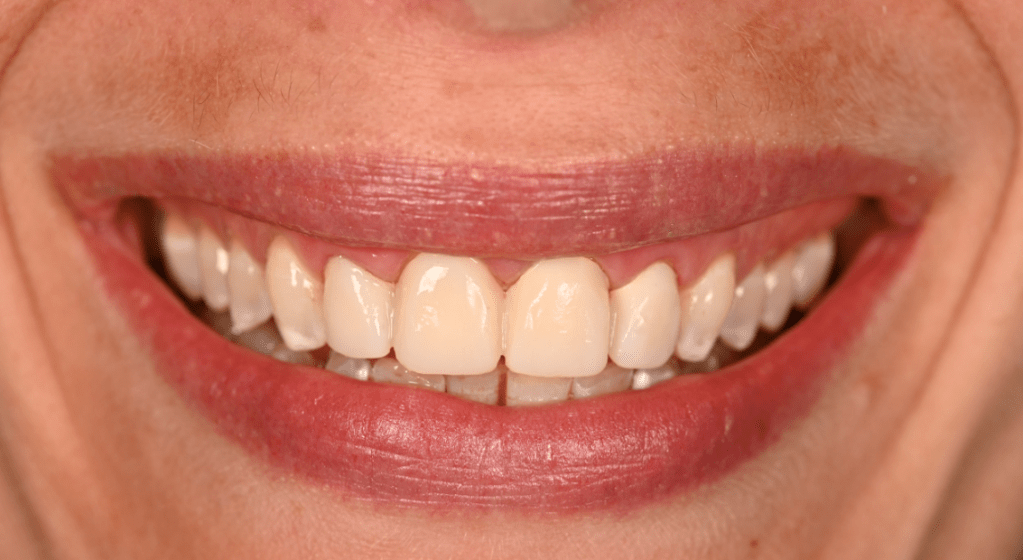

Preparations with shade tab A1, patient requested no characterization in final crowns

Final Restorations Emax Press #6-10, no characterization as requested by patient